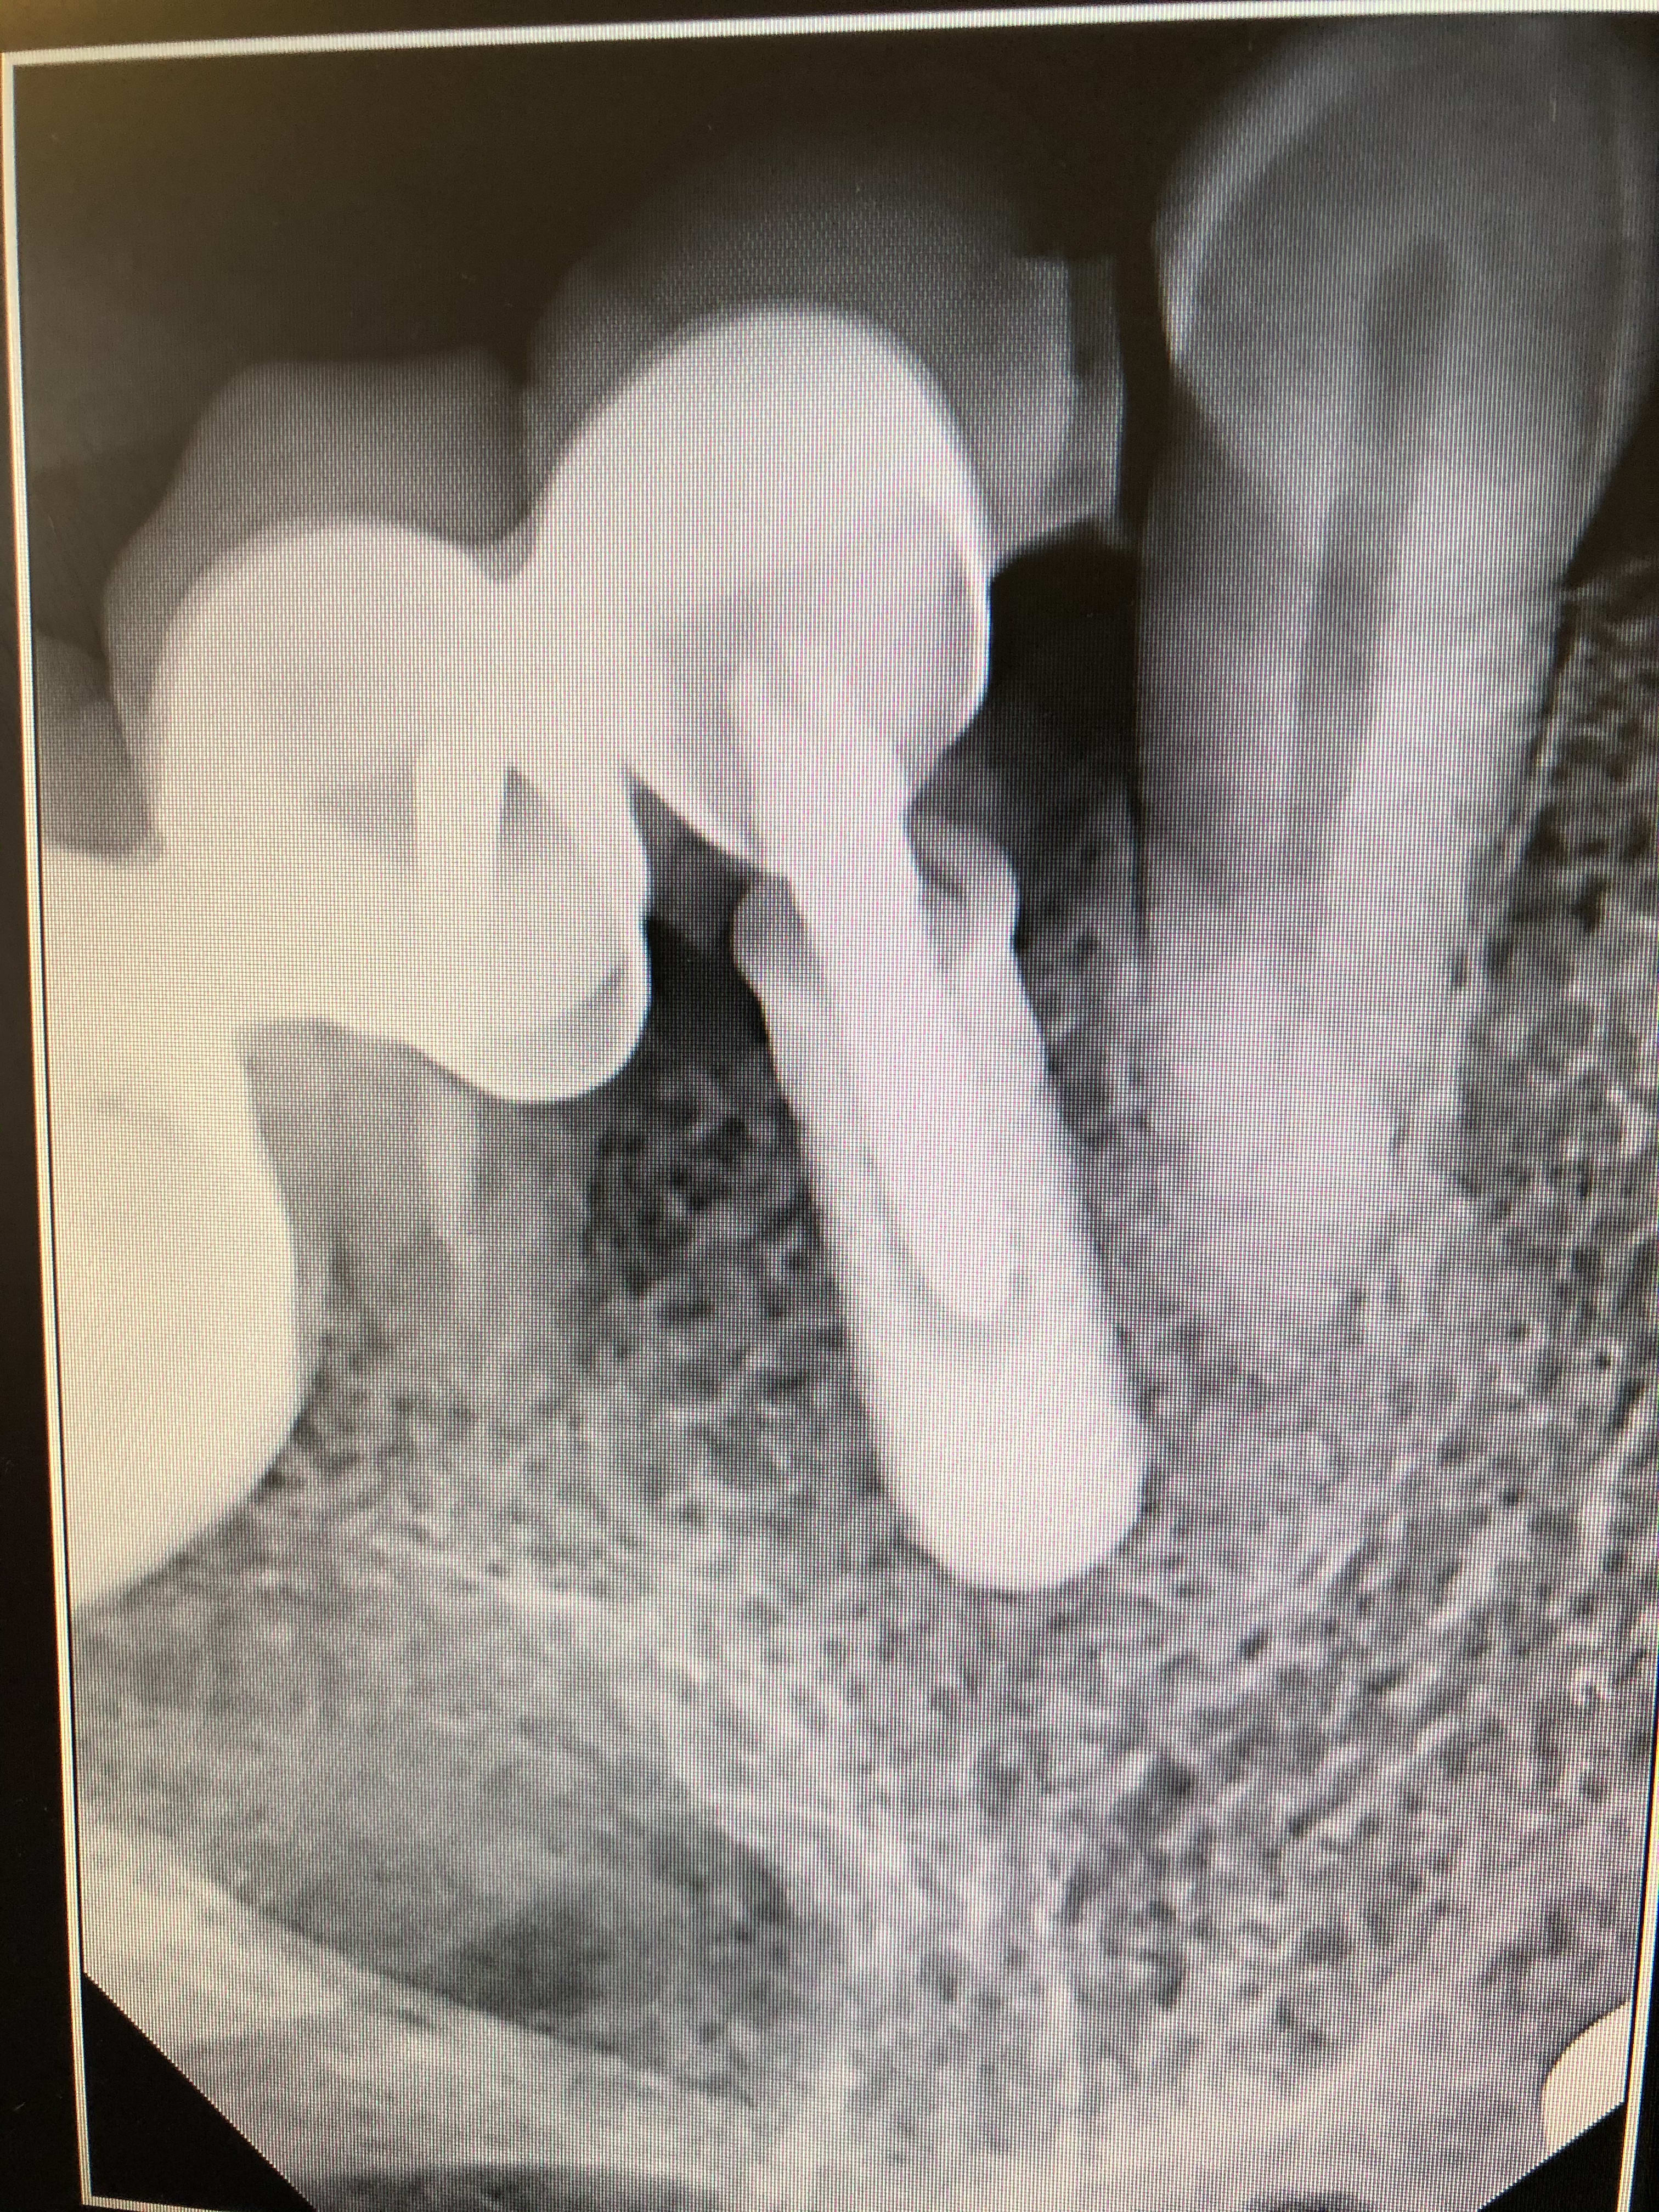

Bonjour j ai fait une radio avec angulateur l image est plus precise j espère que cela sera suffisant pour identifier l implant

28/01/2020 à 13h29

pfff....rien trouvé....

et puis je vais te dire, amha le filetage interne est mort....

j'ai recommencé une recherche hier soir....nada, rien trouvé sur cet implant....

de toutes façons, avec la "bidouille" faite à l'intérieur, le pas de vis est certainement inutilisable, abîmé, usé, plein de ciment/colle